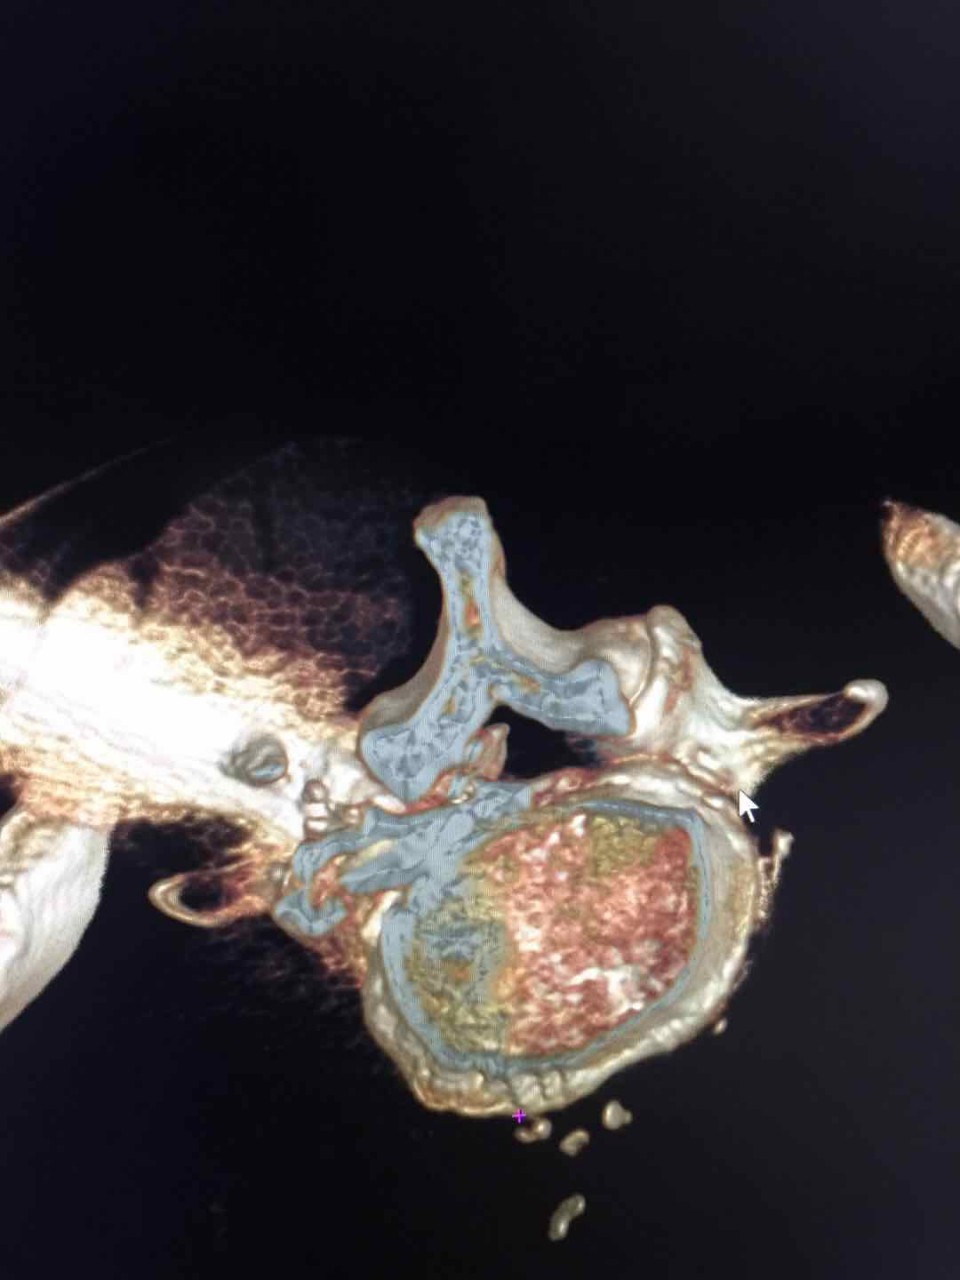

精确造影

家住合肥的患者陈某今年60岁,5月初,陈某搬重物后突然出现腰及右下肢疼痛剧烈不能行走,活动后加重。曾接受保守治疗暂时控制住病情,也自己用膏药敷贴缓解疼痛, 但效果不佳。陈某遂赴省城多家医院就诊,MRI示椎间盘膨出。腰椎退变。药物及康复治疗两天后症状加重。5月10日,陈某及家人随即来到安医大一附院疼痛科就诊。经精确诊断后确诊为极外侧型巨大椎间盘突出。这是非常少见的一种椎间盘突出类型,存在30%的误诊率。入院后陈某对传统腰椎间盘手术抱有极大的恐惧心理。一是担心手术疼痛,二是担心会造成神经损伤之类的并发症。疼痛科副主任医师宋阳通过和陈某对椎间孔镜手术详细介绍后,陈某同意手术。术前给患者做了椎间盘造影,更加准确定位突出位置和节段。术中局部麻醉完善,整个手术患者没有任何不适感觉。且可以清醒的和手术医生交流手术的疑惑。术中医生通过高清显像系统向陈某实时解释了手术目的及效果体现。在清醒舒适的状态下医患共同参与了手术过程,取出巨大椎间盘突出近7cm。如此巨大的极外侧型椎间盘突出实属罕见。

术后,陈某一天后即可下床活动,三天出院。快速康复。整个医疗过程体现出现代疼痛微创技术的三大优势:1. 精准医疗。从术前诊断到术前造影定位到术中靶向放置工作套管到术中精确减压。2.舒适化医疗。整个过程基本无痛。3. 微创化医疗。除去突出物摘除,不破环正常骨质,韧带,脂肪组织。